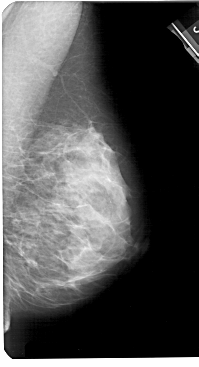

A_1183_1.RIGHT_MLO

RIGHT_MLO LINES 5491 PIXELS_PER_LINE 2971 BITS_PER_PIXEL 12 RESOLUTION 43.5 NON_OVERLAY